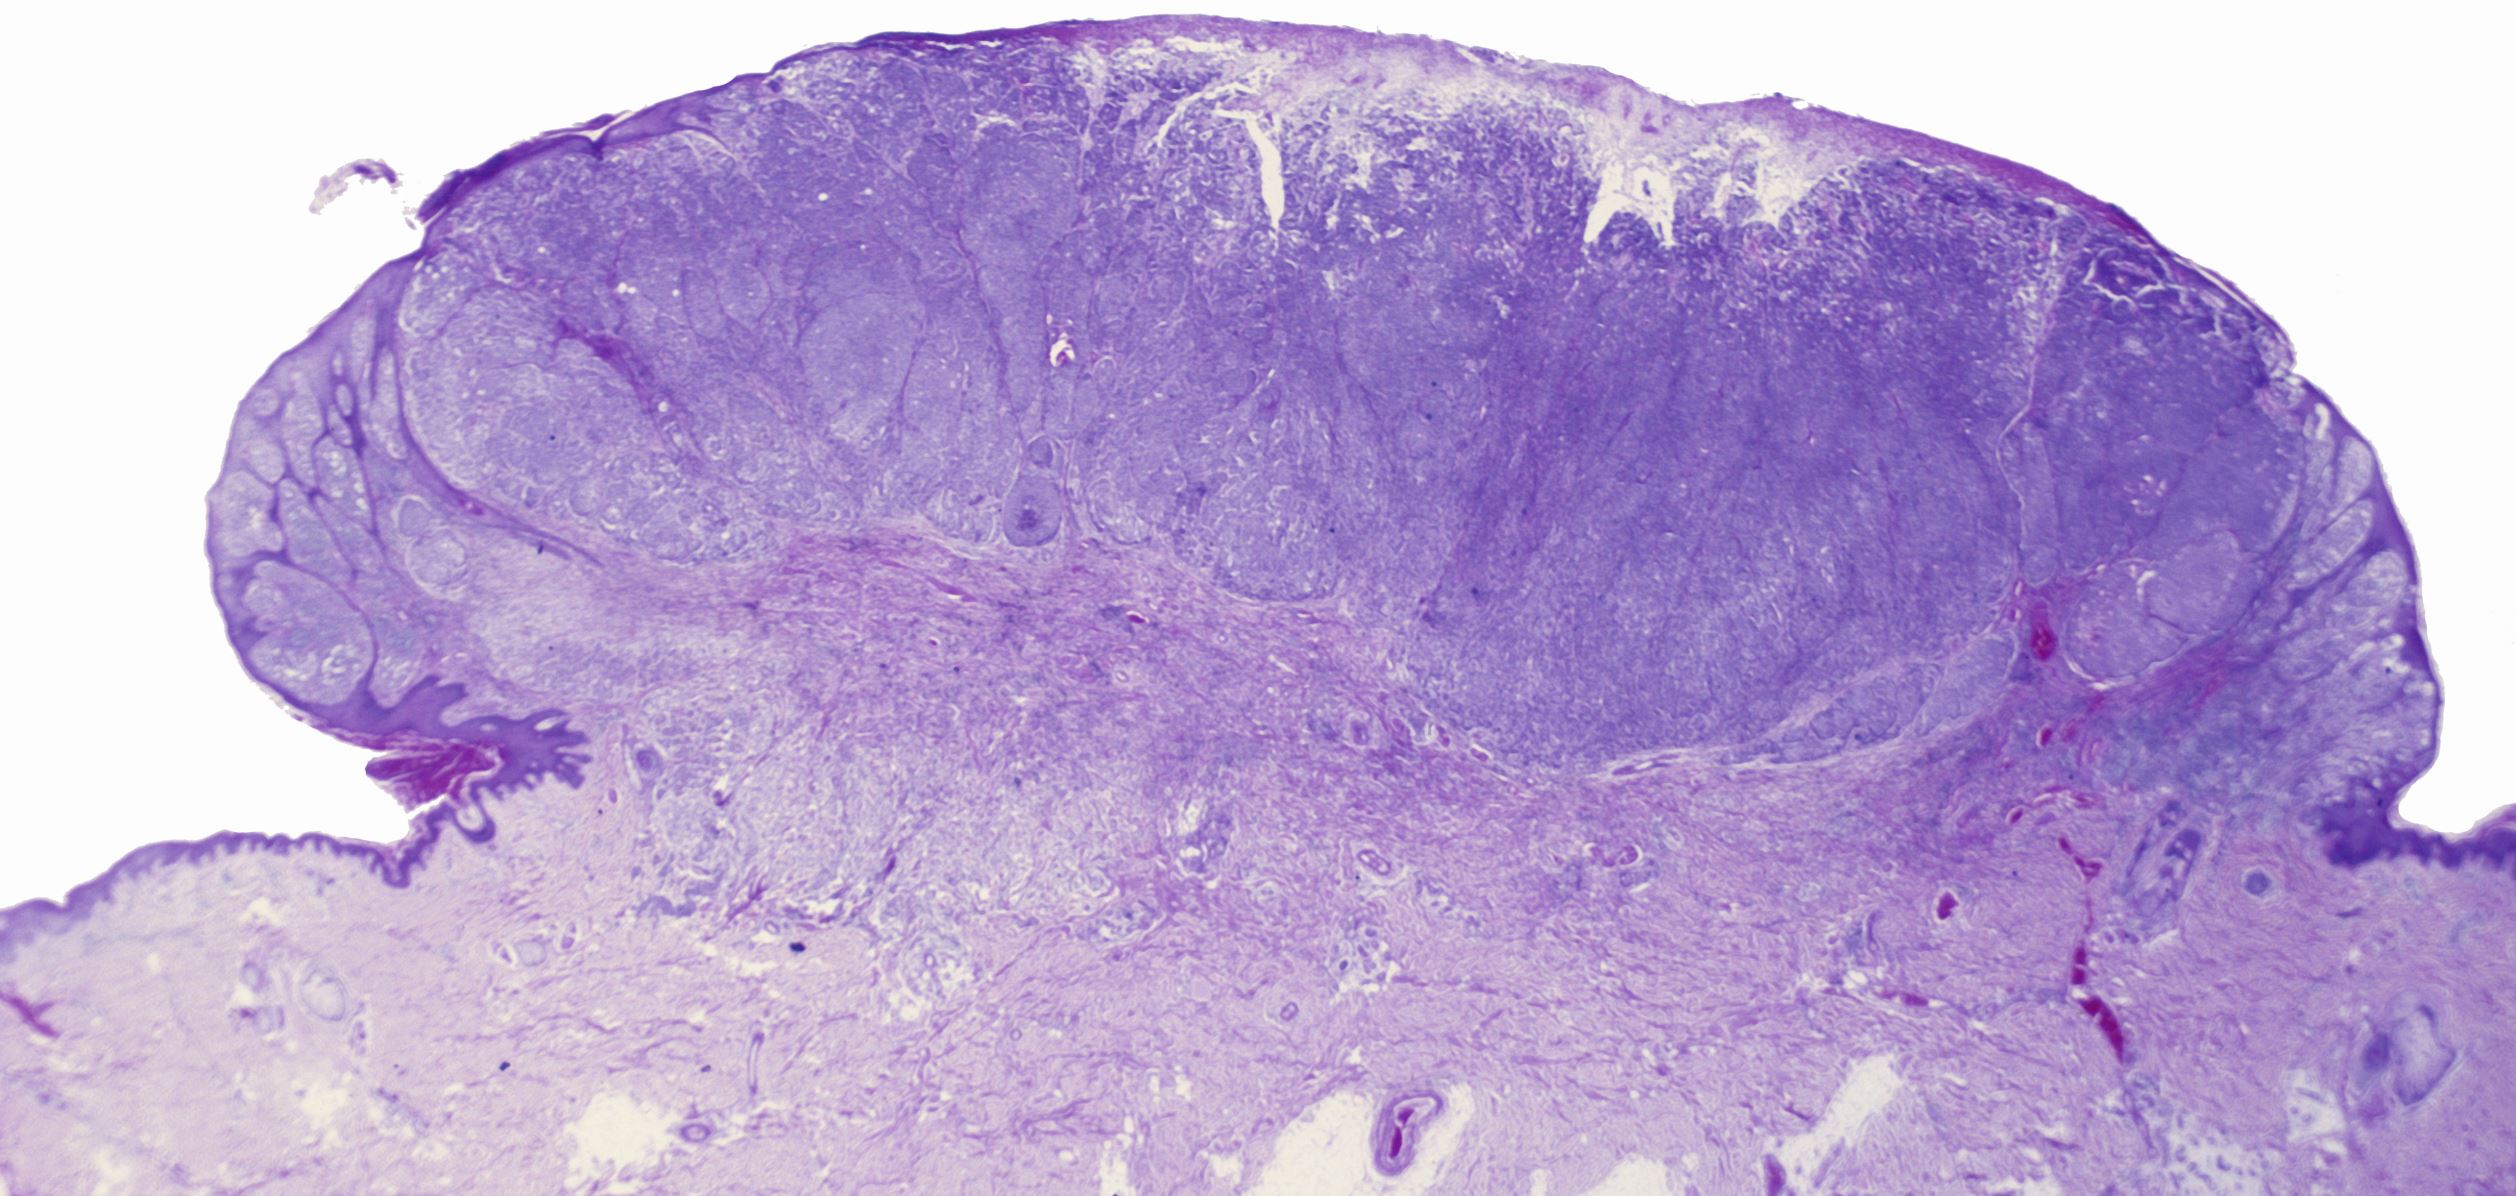

Noduläres malignes Melanom

© Biophoto Associates / Science Photo Library